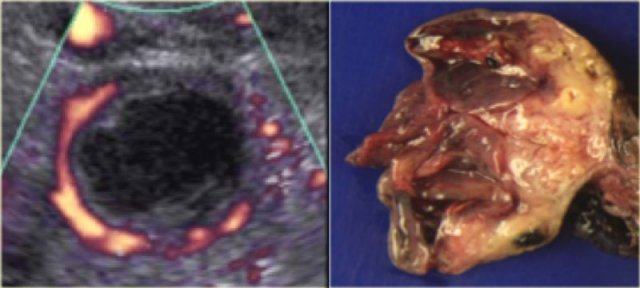

Corpus luteum cyst Corpus luteum cyst

Another case with the typical the 'ring of fire' on ultrasound.

At pathologic examination the collapsed bloody cyst can be clearly seen.

Ultrasound shows a very large multi-loculated cystic lesion in the region of the right adnex.

Some locules are anechoic. Others contain uniform low-level echoes, consistent with proteineous content, such as hemorrhage or, in this case, mucin. The septations are thin, except for the dorsal septations that appear somewhat thicker, partially caused by the lower scanresolution at great depth. The septations are avascular. There are no solid components. There was no ascites.

Despite the absence of solid components and despite the absence of vascularity on color Doppler, the size and the multi-loculated aspect of this lesion are suspicious for a cystic neoplasm and warant further evaluation.

The CECT shows similar findings. The locules are of different attenuation, consistent with varying protein content.

There is no ascites orperitoneal deposits and no lymphadenopathy.

At pathology this was a mucinous cystadenocarcinoma of low malignant potential.

Specimen of the mucinous cystadenocarcinoma Specimen of the mucinous cystadenocarcinoma

The thin, relatively avascular septae, the absence of frank solid components, the absence of ascites and peritoneal carcinomatosis and the absence of invasion, suggest a lesion of low malignant potential (LMP).

Note however, that this diagnosis can not be made on imaging findings alone.

Especially the absence of invasion in ovarian stroma cannot be judged reliably on imaging.